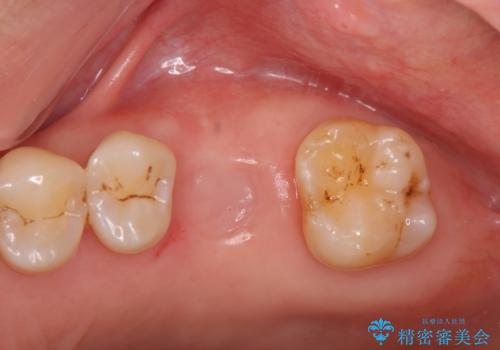

奥歯の欠損 インプラントによる咬合機能回復

- 50代男性

- 治療期間

- 8ヶ月

- 治療回数

- 5-10回

- 奥歯を失い噛めないことの治療を希望され来院されました。